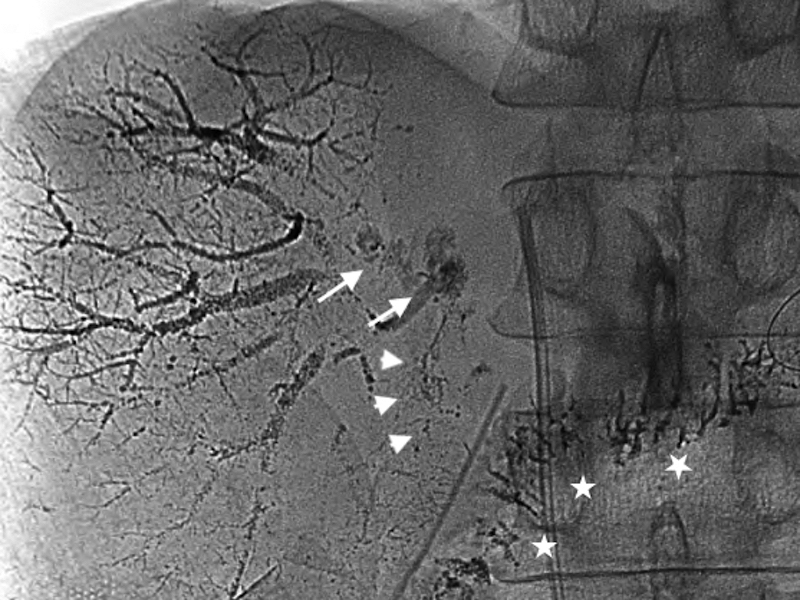

再手術後経過:再手術後はICUに収容し,高度なCOPDを合併していることから人工呼吸器による呼吸管理を行った.また,低タンパク血症に対してアルブミン製剤の投与と利尿剤の投与を行い膠質浸透圧を維持することに務めた.しかし,初回手術28日目に血圧が80 mmHg台に低下し,大量輸液,昇圧剤(ドーパミン製剤,カテコラミン製剤)の投与を行ったが反応に乏しく,同日の尿量は330 mlと乏尿となりpreshock状態と判断した.初回手術29日目にはWinslow孔に挿入していたドレーンからの排液が1,500 mlと増加したため,そのアルブミン濃度を測定すると1.9 g/dl(同日の血清アルブミン値,2.2 g/dl)と高い値を示し,一方トリグリセリドは31 mg/dlと低値であった.以上より,ドレーンの排液は腹水ではなくリンパ漏であり,食事摂取中に全く白濁を認めなかったため乳糜を含む腸管由来のリンパ液ではなく,また大動脈周囲に手術操作が及んでいないため腸骨大動脈リンパ漏は考えにくく,障害肝からの肝リンパ漏の可能性が高いと考えた.そこで,初回手術30日目よりリンパ漏に対する対処としてオクトレオチド酢酸塩300 μg/日の持続皮下注射およびエチレフリン塩酸塩120 mg/日の持続静脈内投与を開始した.同日午後より,大量輸液とアルブミン製剤の積極的な投与がリンパ漏出による循環血漿量の減少に追いつき始めたため血圧は100 mmHg以上となり,尿量も1,000 ml以上確保された.しかし,以後もドレーンの排液は減少せず,初回手術34日目には再手術後経過中最も多い1日1,530 mlに達した.このため,このまま保存的な対処では再びショック状態に陥る危険があると判断し,初回手術36日目に直接肝臓のリンパ管を塞栓する目的でPTLを施行した.エコーガイド下に21 GのPTC針を前区域グリソンに穿刺し,透視下に造影剤イオパミドールを少しづつ注入しながら引き抜くと門脈,胆管が造影された後に肝リンパ管が造影されたため,約5 mlを急速注入した.さらに,リピオドールも続けて注入したが,呼吸性変動により針先が動き,多くは門脈と胆管に流れたが一部はリンパ管内に入ったため手技を終了した.イオパミドール注入後の画像を確認するとリンパ液漏出部位は判然としなかったが,肝前区域から肝門に至るリンパ管が網目状に造影されており,リンパ管の内膜の炎症じゃっ起には有効な手技ができたものと判断した(Fig. 2).また,その後のリピオドール注入後の画像では一部は肝門部から肝十二指腸間膜にかけてのリンパ管にリピオドールがまだらに残存しており,リンパ管の塞栓もなされたものと考えられた(Fig. 3).PTL翌日に撮影した単純CTにて肝十二指腸間膜内にリピオドールの貯留した蛇行するリンパ管が確認された(Fig. 4).PTL施行翌日の初回手術37日目以降はドレーンからの排液量はほぼ半減し,500~600 ml程度となりvital signも安定した.しかし,数日経過を見てもそれ以上の減少傾向を認めなかったため,初回手術42日目,44日目,47日目にWinslow孔ドレーンよりOK-432 10 KEを生理食塩水10 mlに溶かして注入し120分間クランプし,その後解放するという処置を行った.初回手術48日目から,それまでサラサラの無色透明なドレーン排液だったものにフィブリンが混じるようになり,初回手術49日目にドレーン排液が完全にゼロになった.ドレーンが閉塞したためと考えられ,その後軽度な腹部膨満が生じ,エコーで確認するとモリソン窩に液体貯留を認めたが徐々に軽快し,初回手術62日目にドレーンを抜去した.また,アルブミン製剤の投与は初回手術60日目に終了した.初回手術78日目から経口摂取を再開したが腹部膨満は認めず,以後はほぼ順調に経過し,呼吸器リハビリテーションに時間を要したが初回手術152日目に自宅に退院した.手術後の臨床経過をFig. 5に示した.

Fifteen minutes after injection of lipiodol, the injected lipiodol was directed to the hepatic hilum (arrows), and successively to the hepatoduodenal ligament (arrowheads). Most of the injected lipiodol flowed into the portal vein or the hepatic duct. Lipiodol in the jejunum via anastomosis of the hepatic duct and the jejunum was seen (asterisks).